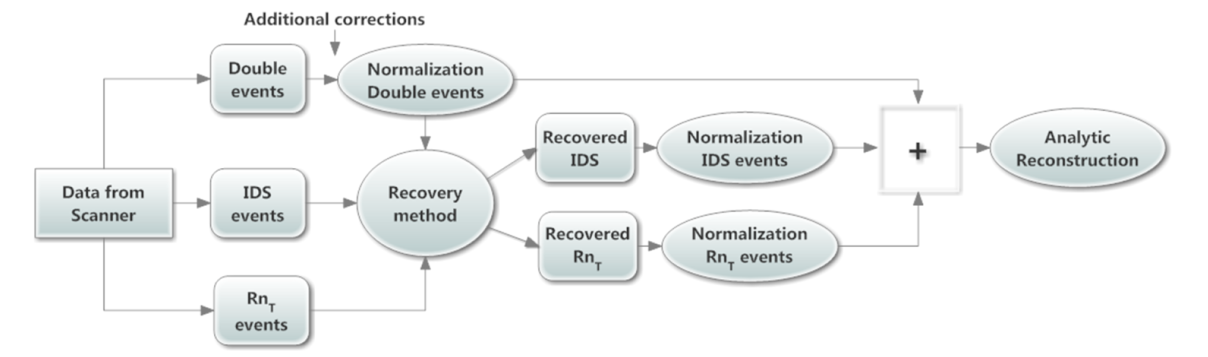

| ABSTRACT | Introduction: Simultaneous in-vivo imaging of several biological processes may improve oncological, neurological and cardiovascular studies by providing complementary information obtained under the same exact conditions and coregistered in space and time. Standard PET imaging does not allow multiplexed acquisitions, as all annihilation photons have the same energy. We developed a technique called multiplexed PET (mPET), which uses a tracer labelled with a pure positron emitter (such as 18 F, 13 N, 11 C), and a tracer labeled with a positrongamma emitter (such as 124 I, 76 Br, 82 Rb, 86 Y). Positrongamma emitters generate a significant number of triplecoincidences , which allows them to be differentiated from the standard PET radionuclides . In this work, we evaluated the performance of mPET using phantom and animal experiments. |

| JOURNAL | IEEE Nuclear Science Symposium & Medical Imaging Conference, 2014 |

| ABSTRACT | Simultaneous noninvasive evaluation of biological processes can improve molecular imaging by providing complementary tissue functions under equivalent conditions coregistered in space and time. Positron Emission Tomography (PET) is the most sensitive noninvasive molecular imaging tool, able to measure many physiological properties with a number of radiotracers. Unfortunately, positron annihilation gamma rays are identical for all radiotracers, making them indistinguishable with standard PET imaging. This fact has motivated attempts at dual tracer imaging with standard PET to distinguish radiotracers using timebased differences. |

Triple coincidences in PET can be used to enable the simultaneous imaging and separation of radiotracers labeled with standard positron emitters (such as 13N) and positron-gamma emitters (such as 76 Br). We have previously shown that multiplexed PET can be achieved without any kinetic modelling or hardware modification, and therefore it can be used in most current PET scanners. The goal of this study was to demonstrate that this methodology can be applied to solve important clinical needs, such as the quantitative measurement of the liquid absorption in the airways, a new biomarker for the treatment response of Cystic Fibrosis (CF) patients. |

| ABSTRACT | Positron emission tomography (PET) is one of the most sensitive noninvasive molecular imaging tool, being its sensitivity several orders of magnitude higher than that typically obtained in single photon emission computed tomography (SPECT). However, PET lacks the ability of SPECT to multiplex signals from several tracers, which is very useful in many different studies such as cardiac imaging with 99mTcSestamibi and 201Tl. Recently, it has been shown that the use of tracers labelled with positrongamma emitter radionuclides like (124I, 86Y, 82Rb, 94mTc, 76Br) in combination with tracers labelled with standard positronemitter radionuclides like (18F, 11C, 13N) enables multiplexed PET (mPET). mPET uses the triple coincidences from the positrongamma emitters, together with the standard double coincidences to reconstruct separated images of each radionuclide’s activity distribution. We obtained encouraging results with mPET in some initial preclinical studies, but a detailed study of the quality and quantification properties of mPET images, and an evaluation of its performance in realistic clinical scenarios was still required. |

| ABSTRACT | Nonstandard PET radionuclides like 124 I, 76 Br, or 86 Y, emit prompt gamma rays together with the positrons which can be detected in coincidence with annihilation photons, creating spurious double coincidences. This causes a background in the PET images that reduces contrast and hampers quantitative accuracy. Existing correction methods are computationally intensive and since they depend on the size of the subject and on the accuracy of a number of complicated estimates, they may be valid for large source distributions only up to a certain size. To overcome these challenges, we have implemented a novel correction which is based on the measurement of positron+gamma triple coincidences. |